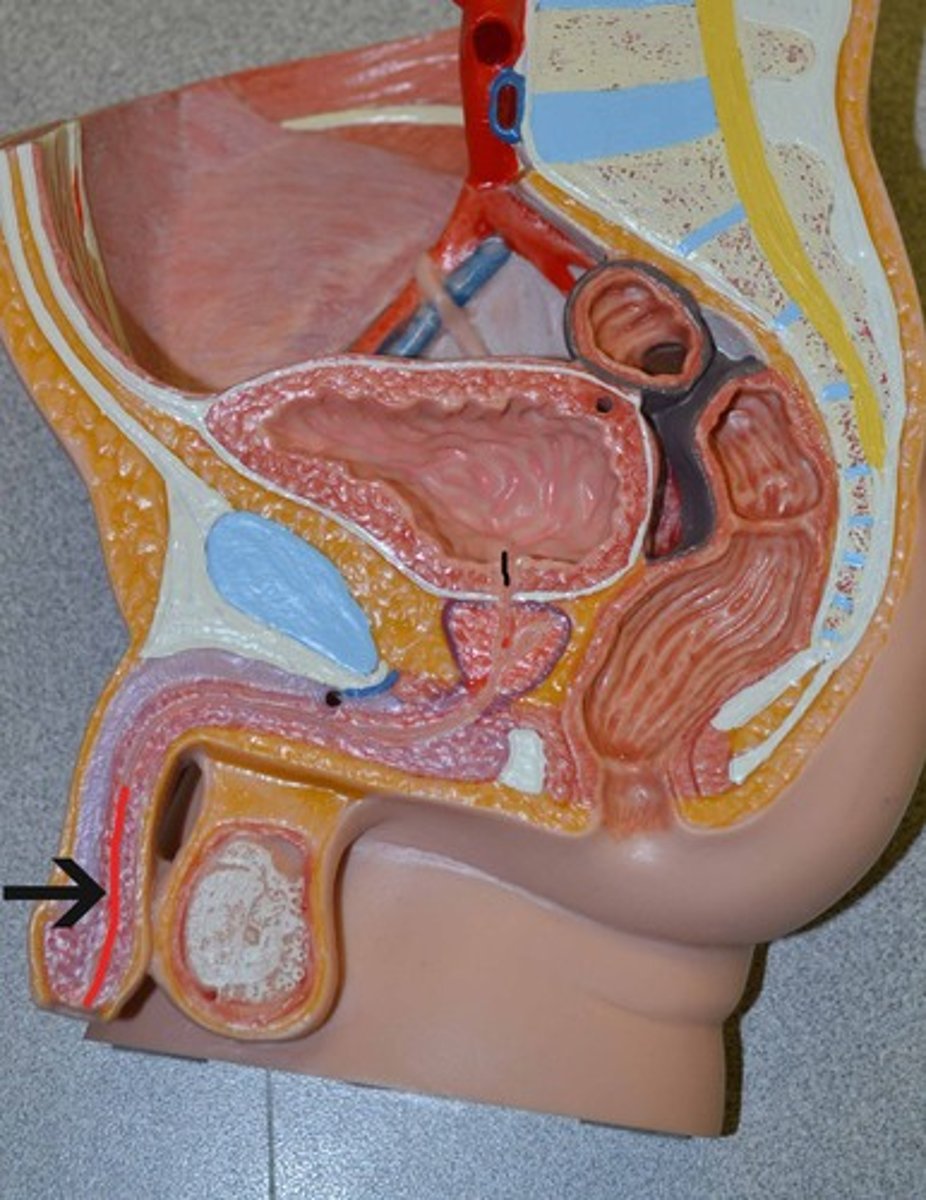

Chapter 30 Anat Phys: Male Reproductive System

Penis

Penis (juvinile)

Penis (post-pubescent)

Erectile tissue

Corpus cavernosum

Corpus spongiosum

External urethral orifice

Prepuce

Glans penis